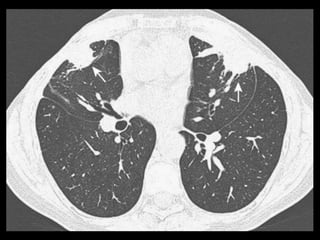

Êmbolo Séptico

TC: modalidade importante para confirmar a

TC: nódulos bilaterais mais numerosos nas regiões

Os nódulos podem ser bem circunscritos ou mal

O sinal do vaso nutriz pode estar presente em 60-

Êmbolo Séptico TC: modalidade importante para confirmar a presença de êmbolos sépticos quando a radiografia convencional de tórax permanece negativa; TC: nódulos bilaterais mais numerosos nas regiões periféricas dos pulmões e nas bases; Os nódulos podem ser bem circunscritos ou mal definidos e com frequência apresentam escavações; O sinal do vaso nutriz pode estar presente em 60- 70% dos casos.